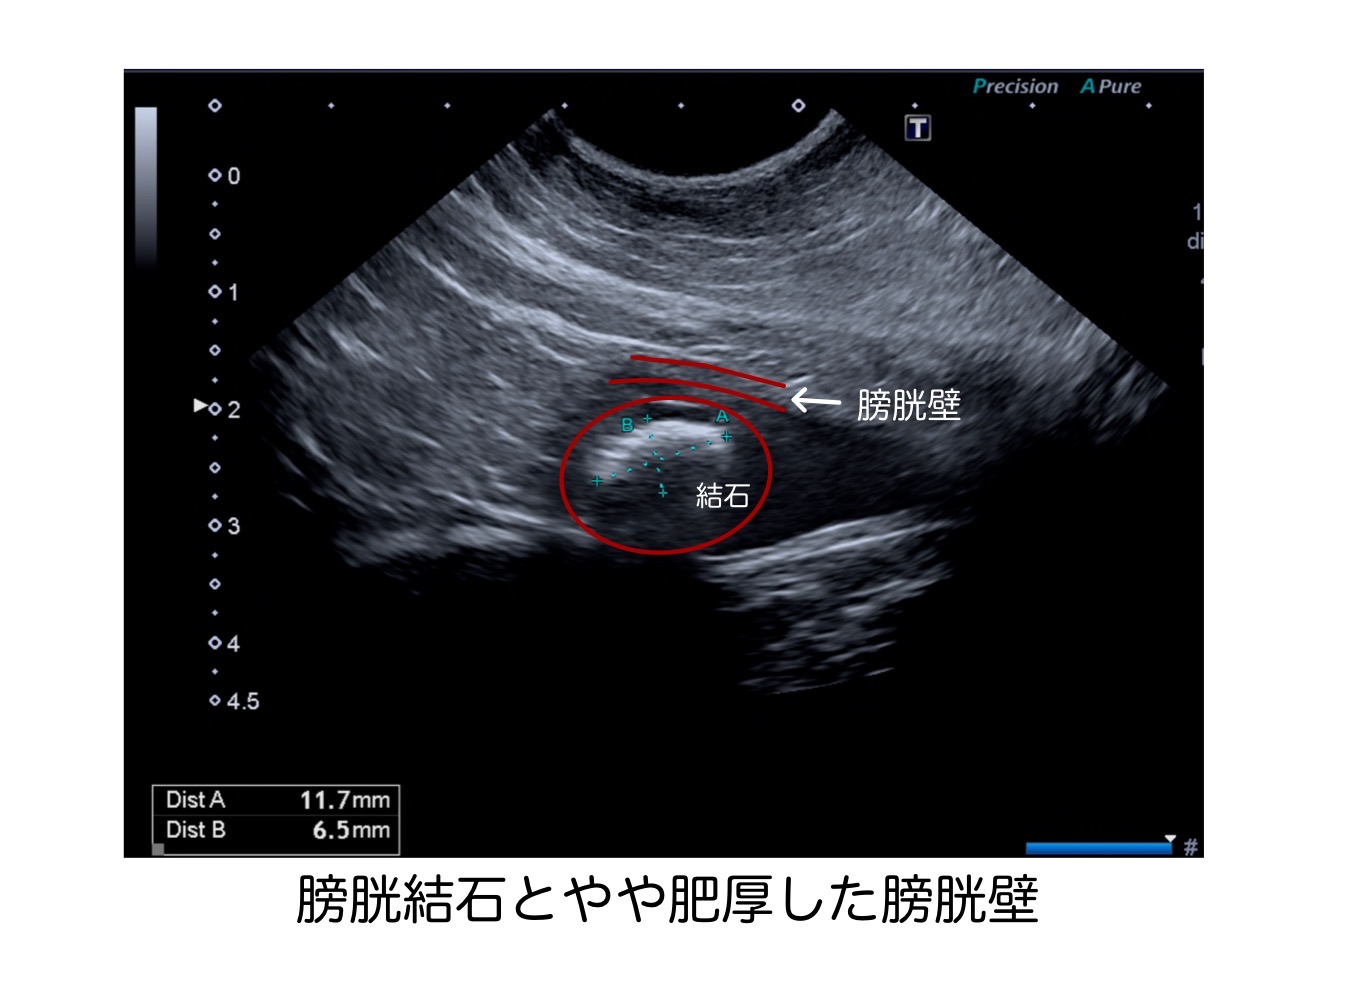

こちらが、手術前のレントゲン検査と超音波検査の結果です。